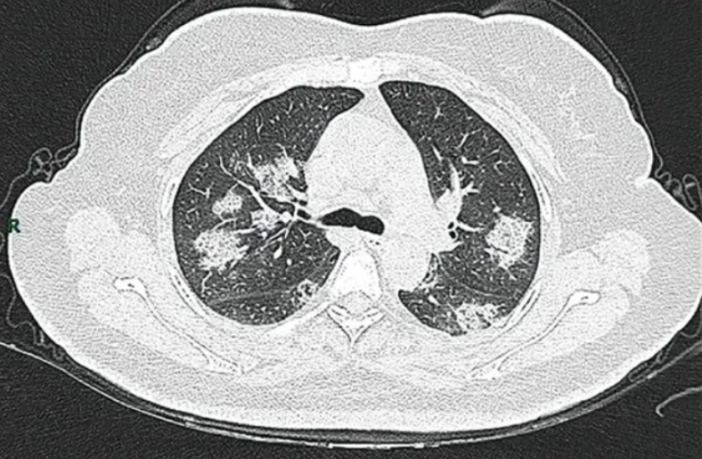

Preview Image: Rapid Pneumonia Progression